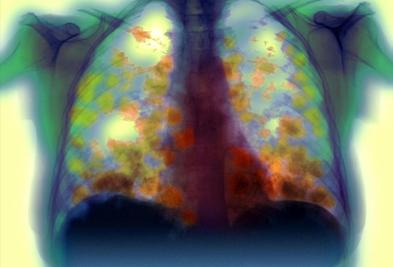

晚期肺癌不能根治,那为什么早期手术可以根治,有些为什么复发? 原创 胡洋大夫 呼吸科胡洋医生 晚期肺癌是指癌细胞转移到其他器官或肺部的转移。只要发生这种情况,就意味着癌细胞已经进入血液或淋巴液。即使切除了可观察到的肿瘤,血液中流动的癌细胞也无法清除,迟早会生长, 2025-05-01

肺癌并不可怕,怕身体不好,有些肺癌诊断后却没有任何方法可以使用。 原创 胡洋大夫 呼吸科胡洋医生 大多数肺癌在早期可以通过手术治愈,在晚期可以通过靶向、化疗、免疫或放疗延长寿命。然而,有些患者由于各种原因无法使用任何方法,尤其是一些早期肺癌患者,诊断后无法进行手术治 2025-05-01